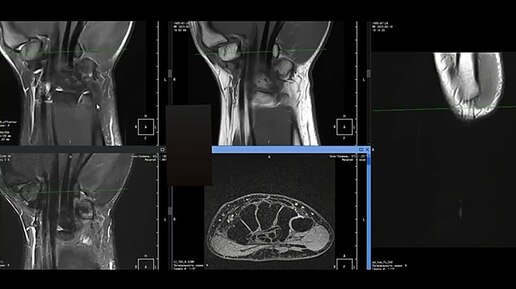

МРТ лучезапястного сустава